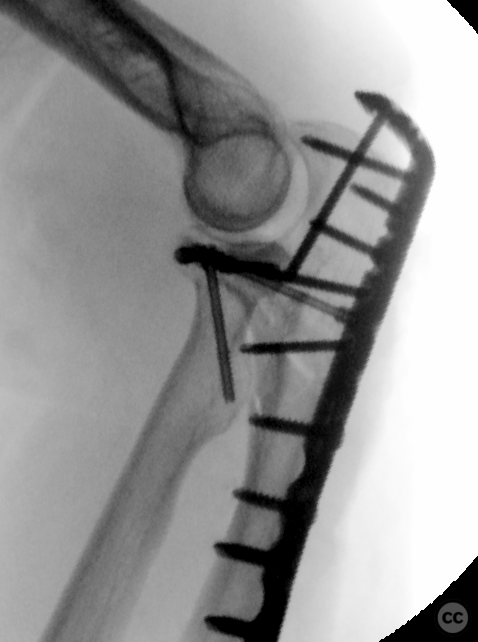

Sep 27 2024

By Dr Ed Oates

Monteggia Fracture with Segmental Ulna S...

Schleswig Holstein, Germany

Ulna - AO/OTA 2Ux